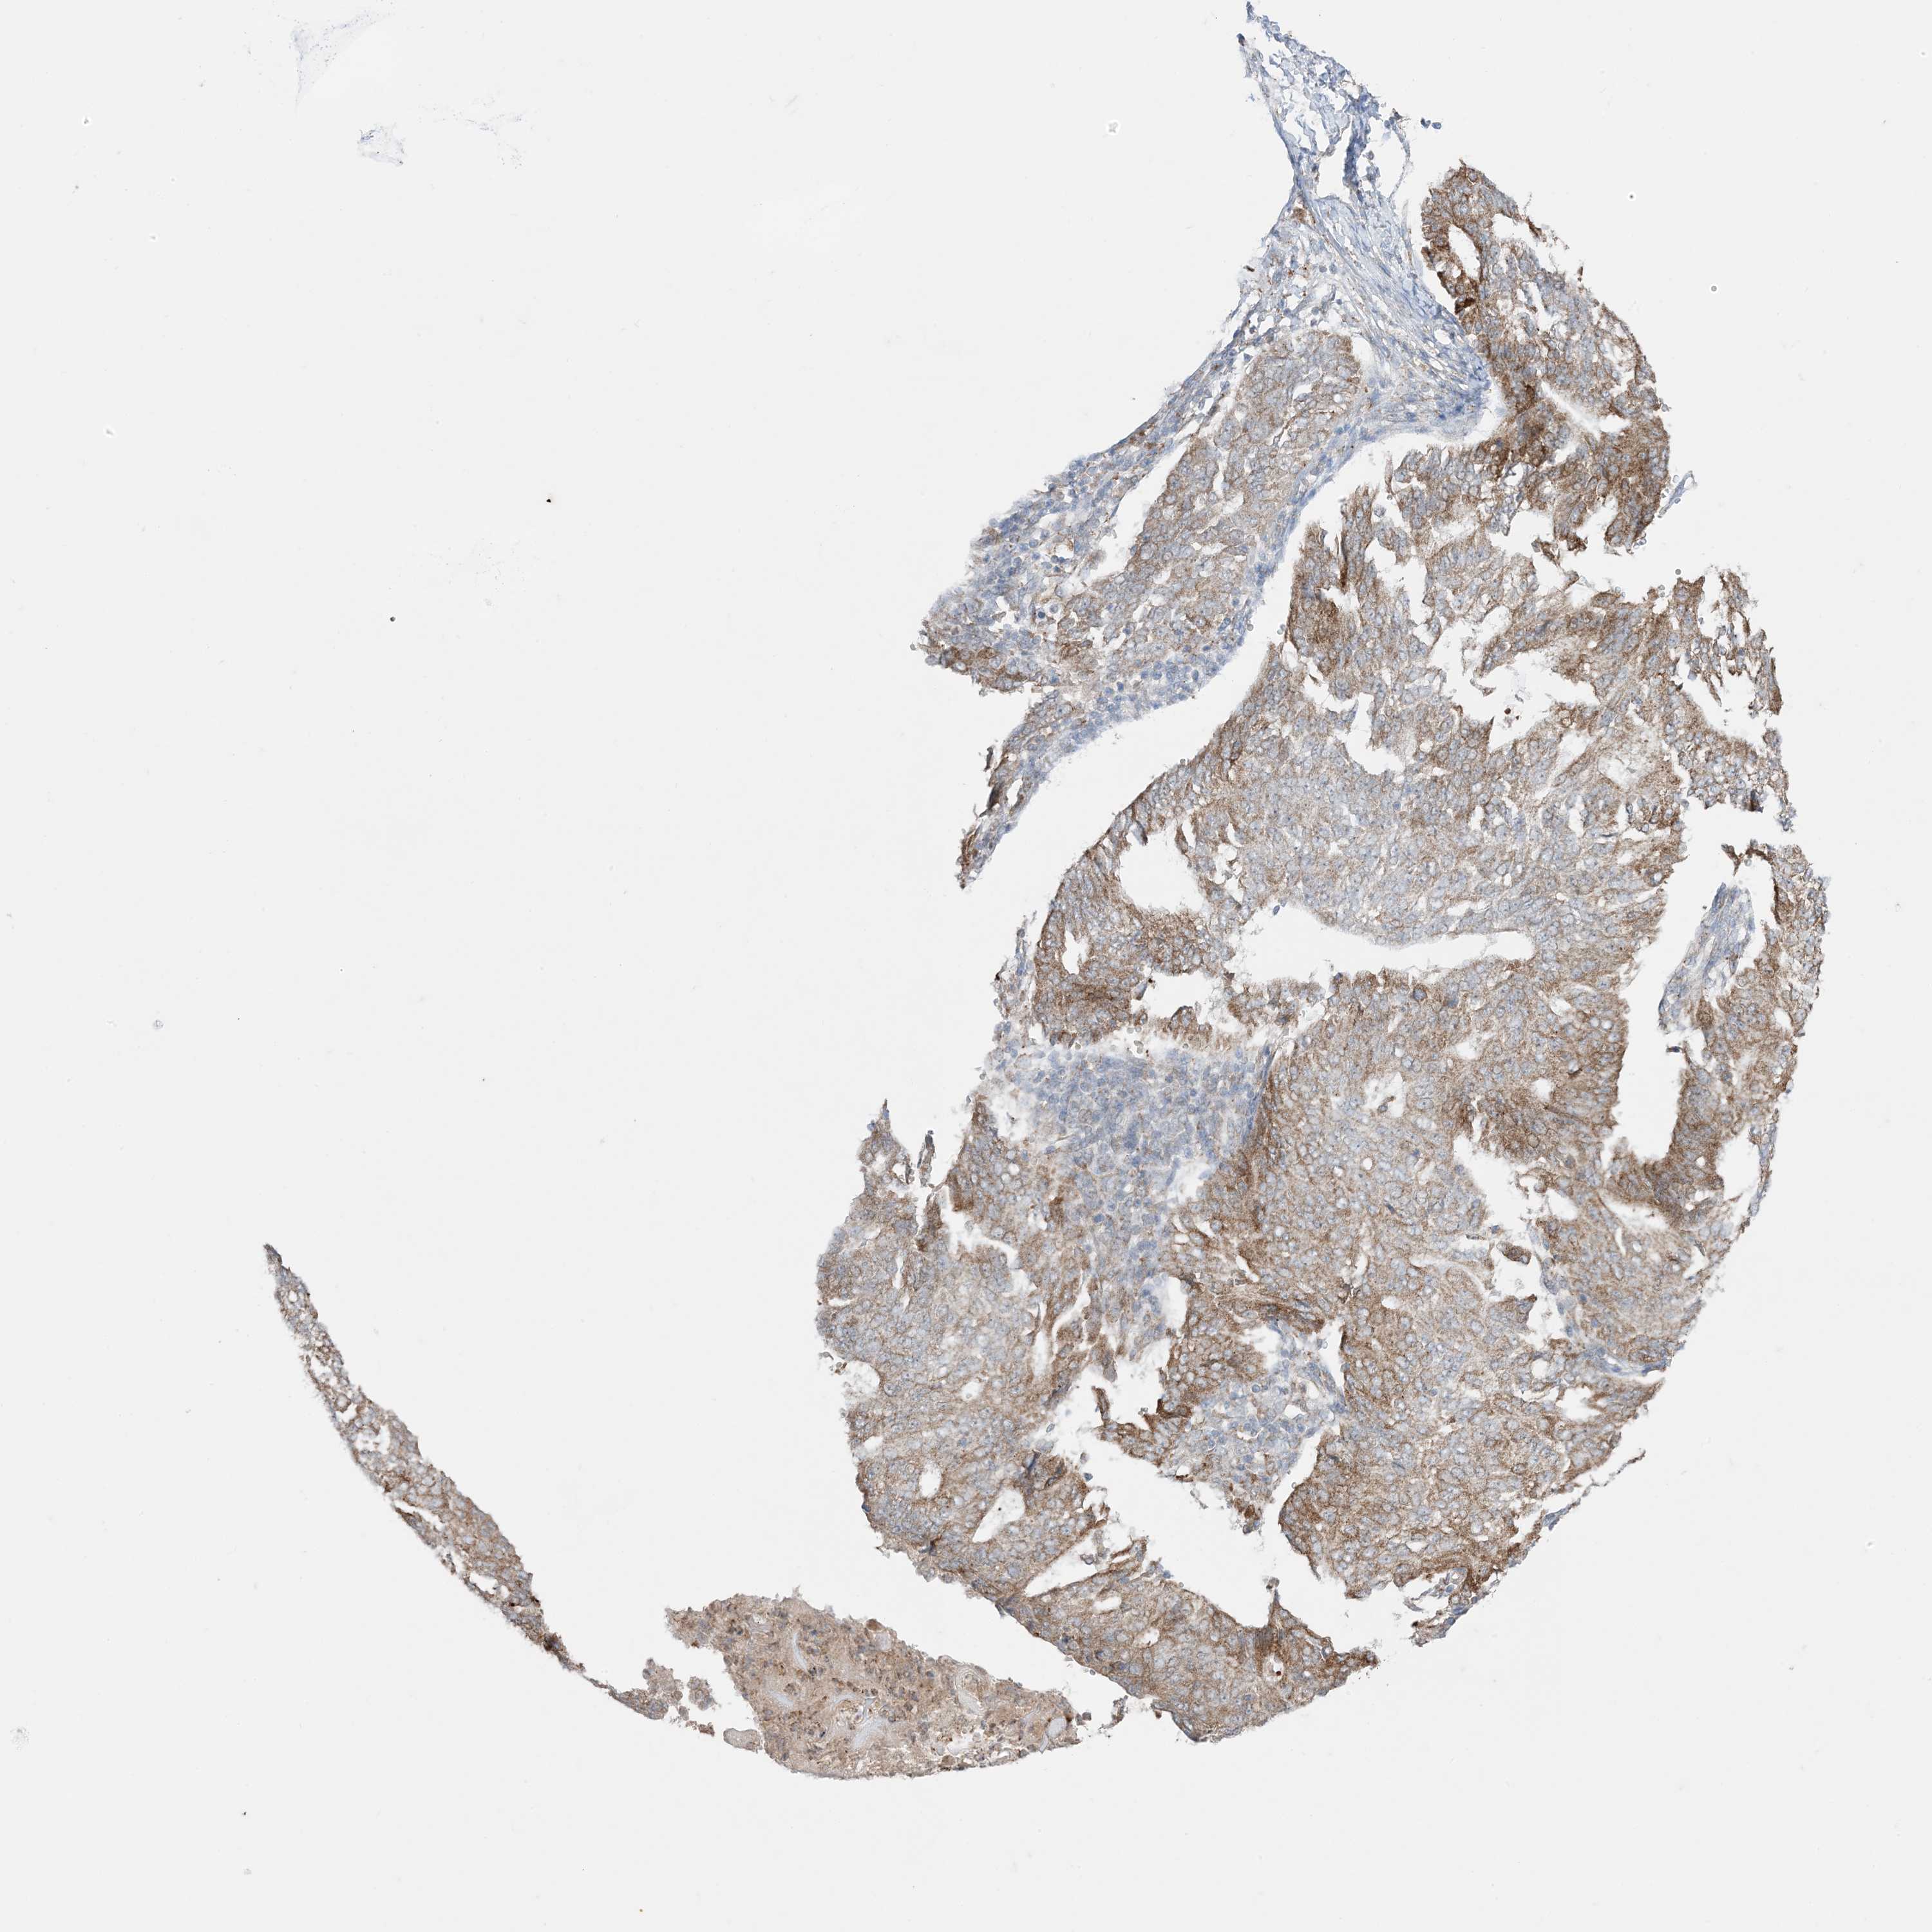

ENDOMETRIAL CANCER - Protein expressioni

A mouse-over function shows sample information and annotation data. Click on an image to view it in a full screen mode. Samples can be filtered based on level of antibody staining by selecting one or several of the following categories: high, medium, low and not detected. The assay and annotation is described here.

Note that samples used for immunohistochemistry by the Human Protein Atlas do not correspond to samples in the TCGA dataset.

Antibody stainingi

Antibody staining in the annotated cell types in the current human tissue is reported as not detected, low, medium, or high, based on conventional immunohistochemistry profiling in selected tissues. This score is based on the combination of the staining intensity and fraction of stained cells.

Each image is clickable and will lead to virtual microscopy that enables deeper exploration of all samples and also displays staining intensity scores, fraction scores and subcellular localization as well as patient and tissue information for each sample.

Antibody HPA001536

Antibody CAB035996

Staining

High

Medium

Low

Not detected

Intensity

Strong

Moderate

Weak

Negative

Quantity

>75%

75%-25%

<25%

None

Location

Nuclear

Cytoplasmic/membranous

Cytoplasmic/membranous,nuclear

Adenocarcinoma, NOS

Neoplasm, malignant, NOS

Adenocarcinoma, metastatic, NOS